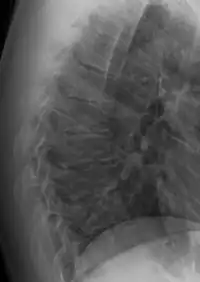

| Scheuermann's disease on lateral Xray of the T spine | |